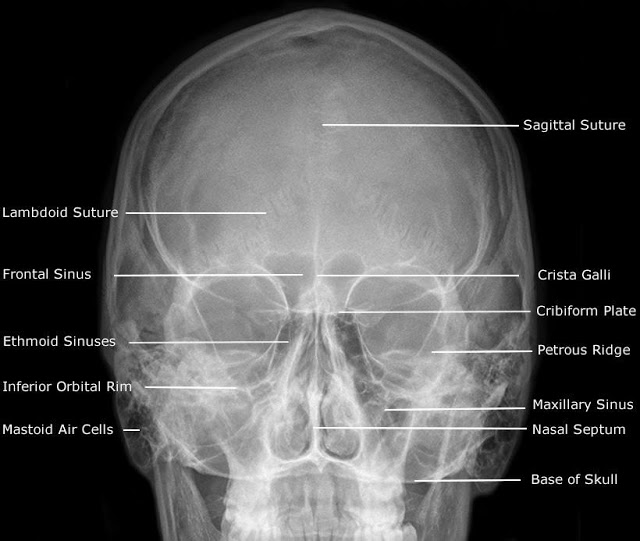

Hmm, after looking at the x-ray and comparing it to the info about the actress's height and such (which is the character's), and then looking up an anatomy chart this could only be just-prior to the critter emerging. It's size and placement would mean serious to fatal compromise of lung and cardiac function from the pressure it'd be causing on those organs.

No they don't, they don't even show up like that on an MRI. The eyes, definitely photoshopped in to lend 'recognizability' to the x-ray image, as one would expect in a Promotional material.